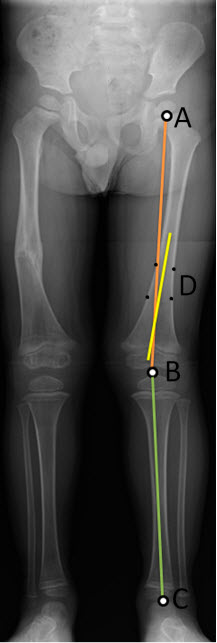

- Κάντε κλικ σε τρία σημεία στο περίγραμμα της οστεοποιημένης κεφαλής του μηριαίου. (Το κέντρο εμφανίζεται ως A στο διάγραμμα.)

- Κάντε κλικ στην περιφερική επίφυση του μηριαίου (Β στο διάγραμμα).

- Κάντε κλικ στην τροχιλία αστραγάλου (C στο διάγραμμα).

Σχηματίζεται μια γραμμή ανάμεσα στην επίφυση του μηριαίου και την τροχιλία αστραγάλου. Επίσης σχηματίζεται μια γραμμή που επισημαίνει τη γωνία ανάμεσα στις δύο γραμμές.

Οι γραμμές στην εφαρμογή εμφανίζονται σύμφωνα με τις προεπιλογές χρωμάτων του συστήματος. Το διάγραμμα χρησιμοποιεί διαφορετικά χρώματα προς αποφυγή αμφισημίας.